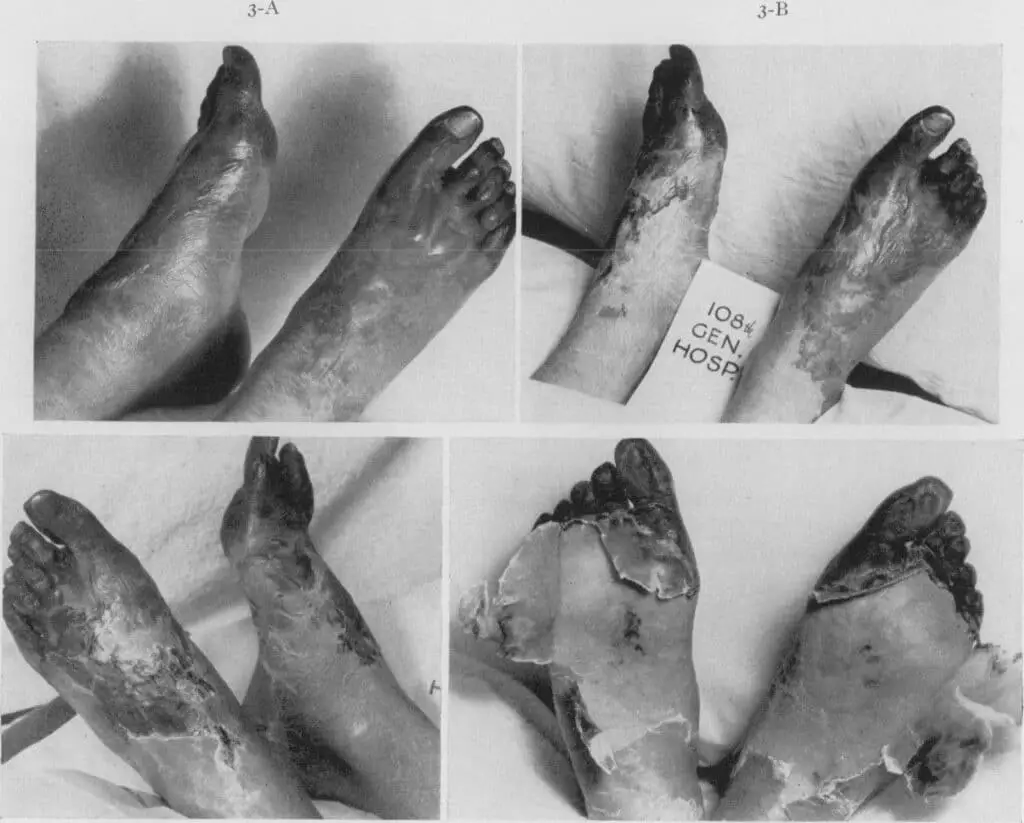

Trench foot, or more accurately immersion foot, is a byproduct of continued damp exposure of the feet in non-freezing, but cold conditions, resulting in initially non-infectious skin damage that frequently becomes infected and in severe cases, progresses to gangrene with resultant need for amputation.

Bacterial Gas Gangrene is typically caused by clostridial bacteria that generate gas bubbles in dead tissue, hence the name. Present in soil, these organisms were frequent contaminants of war wounds caused by the extensive soil disruption from shelling and trenching.

In 1914 12% of British war wounded had this infection. By 1918, it decreased to less than 1%, all secondary to more rapid wound debridement of devitalized (dead) tissue, expedient evacuation from the battlefield, and a better understanding of the disease.